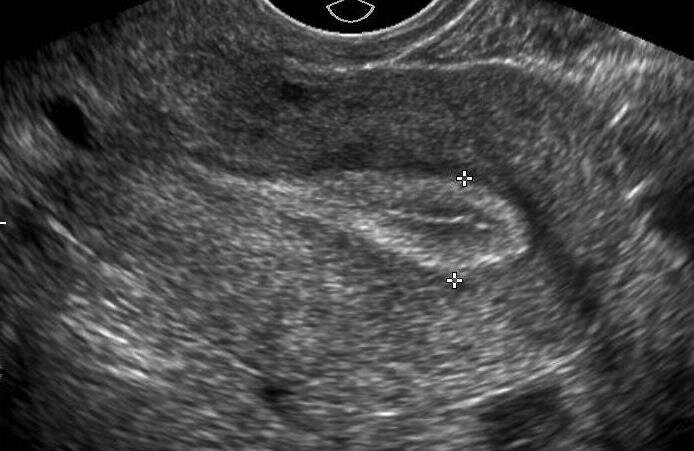

Тонкий эндометрий (≤ 7 мм) в поздней фолликулярной фазе может быть связан с неудачной имплантацией.

Несмотря на то, что толщину эндометрия (ТЭМ) обычно оценивают до и контролируют во время циклов ЭКО, анализ толщины эндометрия и и его УЗ-структуры может быть рассмотрен при ПНИ.

В систематическом обзоре и метаанализе (Ляо и др., 2021), изучающем связь между толщиной эндометрия и показателями живорождения в свежих циклах, сообщалось, что у женщин с тонким эндометрием (ЭМТ<7 мм) был значительно более низкий процент живорождения по сравнению с женщинами с ТЭМ>7 мм (OR 0.47, 95% CI 0.37-0.61).

О связи между толщиной/структурой эндометрия и частотой наступления беременности также сообщалось при переносе замороженных эмбрионов и циклах стимуляции (Nishihara, et al., 2020, Shalom-Paz, et al., 2021). В исследовании было обнаружено, что вероятность клинической беременности в следующем цикле у женщин с тонким эндометрием значительно ниже по сравнению с женщинами с толщиной эндометрия > 7 мм, с положительной и отрицательной прогностической ценностью 77% и 48%. % соответственно (Kasius, et al., 2014). После исключения искажающих факторов потенциальная независимая связь толщины эндометрия с результатами лечения ВРТ была признана слабой (Griesinger et al., 2018, Yuan et al., 2016).